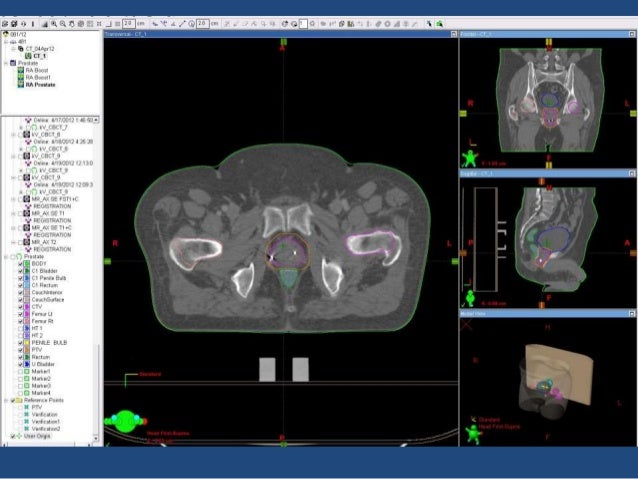

Proton therapy is similar to radiation therapy, but it offers a more targeted approach. It may also be called proton beam therapy. The most recent statistics released by the american cancer society states that prostate cancer will be the most commonly diagnosed cancer in american men in 2013 with an estimated 238,590 new cases and 29,790 deaths [].among treatment options available for prostate cancer, volumetric modulated arc therapy (vmat) and proton therapy are two of the.

This can damage nearby healthy tissues and can cause significant side effects. Proton therapy is a type of radiation that uses a particle, the proton, to deliver radiation while keeping the dose low to nearby healthy tissue. Present data have demonstrated that proton beam therapy is safe and effective compared with the standard treatment options for prostate cancer.

By contrast, proton therapy delivers a beam of proton particles that stops at the tumor, so it’s less likely to damage nearby healthy tissues. This lowers the effects of radiation on healthy tissue surrounding the tumour.